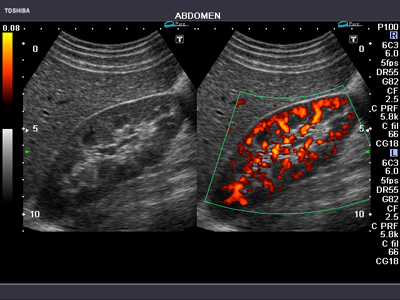

生体からの反射波に含まれる高調波で画像構成するTHI(Tissue Harmonic Imaging)を搭載。腹部,心臓のほか,小児や表在用の高周波プローブでも鮮明な画像を提供します。 複数の信号を合成することによりアーチファクトの少ないクリアな画像を実現するApliPure™は,カラードプラやパワードプラとの組み合わせも可能です(図7)。

図7 腎臓血流のパワードドプラ画像